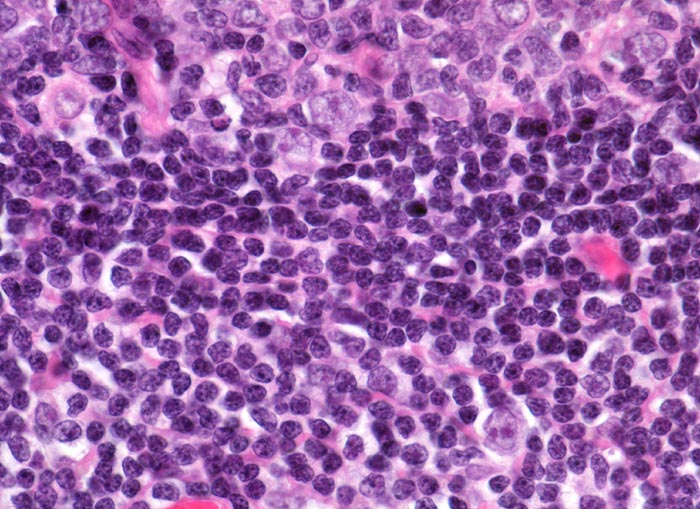

Oben im Bild ein Keimzentrum mit Zentrozyten, Zentroblasten und follikulär dendritischen Zellen. Angrenzend die zelldichte Mantelzone. Unten im Bild die lockerer konfigurierte Marginalzone mit eingestreuten dendritischen Zellen mit sternförmigen Zytoplasmaausläufern und Blasten mit grossen Kernen.

Perikolischer tumorfreier Lymphknoten aus dem Abflussgebiet eines wenig fortgeschrittenen Kolonkarzinoms.